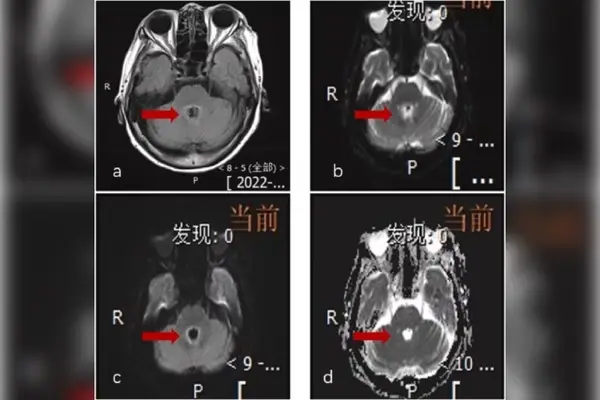

Os exames mostraram, de fato, uma lesão no cérebro. No entanto, após 9 dias de internação, a equipe realizou uma punção lombar e o exame revelou que ela estava infectada com a Balamuthia mandrillaris, uma ameba rara que pode alcançar o cérebro. De acordo com a literatura médica, esse parasita mata nove em cada 10 pacientes.